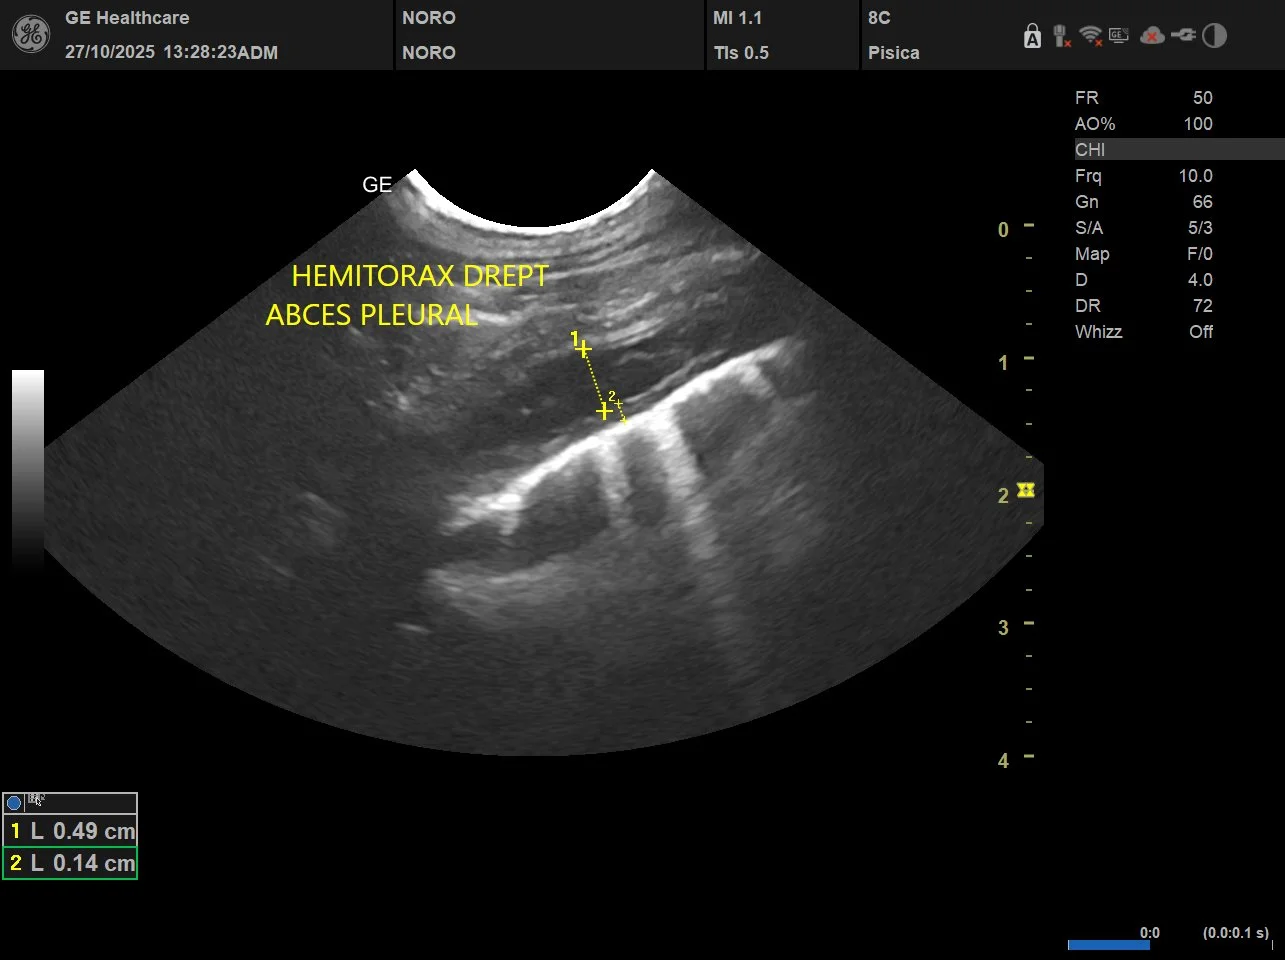

Ecografia toracică este o investigație imagistică neinvazivă care folosește ultrasunete pentru a evalua structurile din interiorul toracelui. Prin ecografie, medicul poate evalua în timp real plămânii, pleura, spațiul pleural, mediastinul, diafragma și, în anumite condiții, structurile cardiace. Procedura nu utilizează radiații ionizante, este nedureroasă și, în majoritatea cazurilor, nu necesită sedare.Pentru utilizare uzuală, ecografia toracică ajută la identificarea acumulărilor de lichid în jurul plămânilor, a modificărilor de țesut, a maselor sau a inflamațiilor. De exemplu, la o pisică care respiră dificil după un episod de stres, medicul poate depista rapid un revărsat pleural și poate decide pașii următori. La un câine în vârstă, ecografia poate oferi indicii despre o afecțiune cardiacă sau despre prezența unei formațiuni care necesită evaluări suplimentare.

Ecografia toracică se realizează în timp real, iar medicul observă imediat structurile examinate. Acest lucru permite ajustarea rapidă a investigației în funcție de ce apare pe ecran. De exemplu, dacă se observă lichid în cavitatea toracică, medicul poate evalua cantitatea și distribuția acestuia.Interpretarea rezultatelor ține cont de contextul clinic. O imagine ecografică nu se analizează izolat, ci în corelație cu simptomele, istoricul medical și alte teste efectuate. În unele cazuri, ecografia ridică suspiciuni care necesită confirmare prin analize de laborator sau prin alte metode imagistice. Pentru proprietari, este util de știut că medicul explică pe înțelesul lor ce a observat și ce înseamnă aceste descoperiri pentru sănătatea animalului. Întrebările sunt binevenite, iar clarificările ajută la înțelegerea pașilor următori.

Proprietarii întreabă adesea de ce medicul recomandă ecografie și nu radiografie sau invers. Fiecare metodă are indicații clare. Radiografia oferă o imagine statică, utilă pentru evaluarea structurii generale a toracelui. Ecografia, în schimb, permite observarea mișcărilor și a lichidelor în timp real. De exemplu, un revărsat pleural mic poate fi dificil de apreciat din punct de vedere radiologic, dar apare clar la ecografie. În schimb, leziunile profunde ale parenchimului pulmonar se văd mai bine radiologic. Medicul alege metoda care răspunde cel mai bine întrebării clinice, fără a expune inutil animalul la investigații suplimentare.